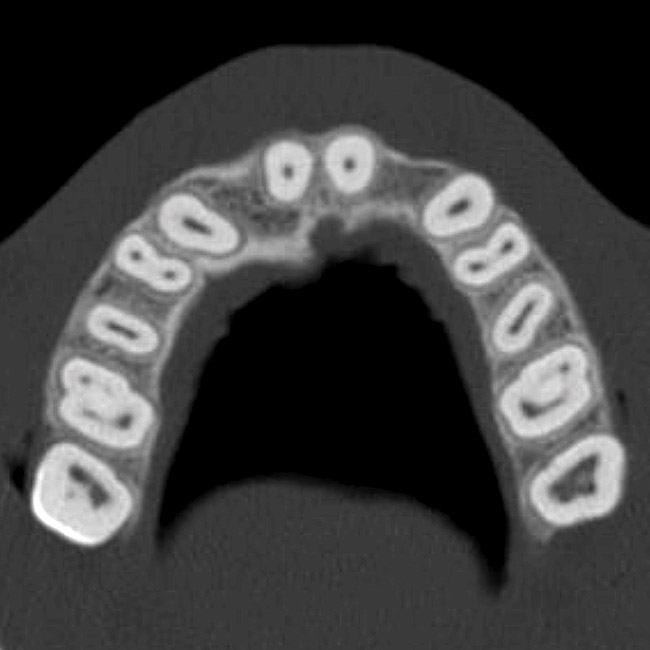

The CT axial views represent an important instrument in gaining a better understanding of anatomical features that cannot be determined by any other imaging modality (Figure 10). When the maxilla is sliced axially at the level where the roots meet the crest of the bone, the adjacent and surrounding root morphology can be revealed. Of note are the individual and different shapes of each of the central incisors, canines, premolars, and molar roots. These images reflect a phenomenon defined by the author as the “restorative dilemma.” Clinicians encounter this often difficult dilemma when attempting to re-establish morphologically correct emergence profiles in prosthetic teeth as they ascend from the round shape of the implant(s). When planning for the placement of the implant in the left lateral incisor area, there appeared to be adequate mesial-distal space between roots as seen in the axial view of Figure 11. A closer inspection of the planned site for the right lateral incisor revealed a more narrow space, further complicated by the distal rotation of the palatal aspect of the tooth root. Based on this preliminary position, the 3.75-mm diameter, straight-walled implant can be seen encroaching on the lamina dura periodontal ligament space of the right canine and central incisor. If there was not adequate room for this diameter and type of implant, the adjacent teeth could sustain potential iatrogenic damage. Therefore, additional “tweaking” of the virtual placement was necessary to diminish this risk.

Figure 10  SOFTWARE IMAGING By slicing the maxilla axially, the images revealed the differing morphology of the central incisors, canines, premolar, and molar roots.

Figure 10